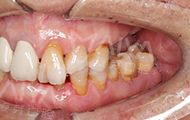

2018年5月28日 麦芽特聘专家孙海鹏博士亲诊设计种植方案

找到麦芽特聘专家孙海鹏博士,我觉得我的牙齿迎来了"柳暗花明"。孙海鹏博士根据我的牙齿情况为我定制了微创无痛种植的方案,我很满意,当天就进行了手术。